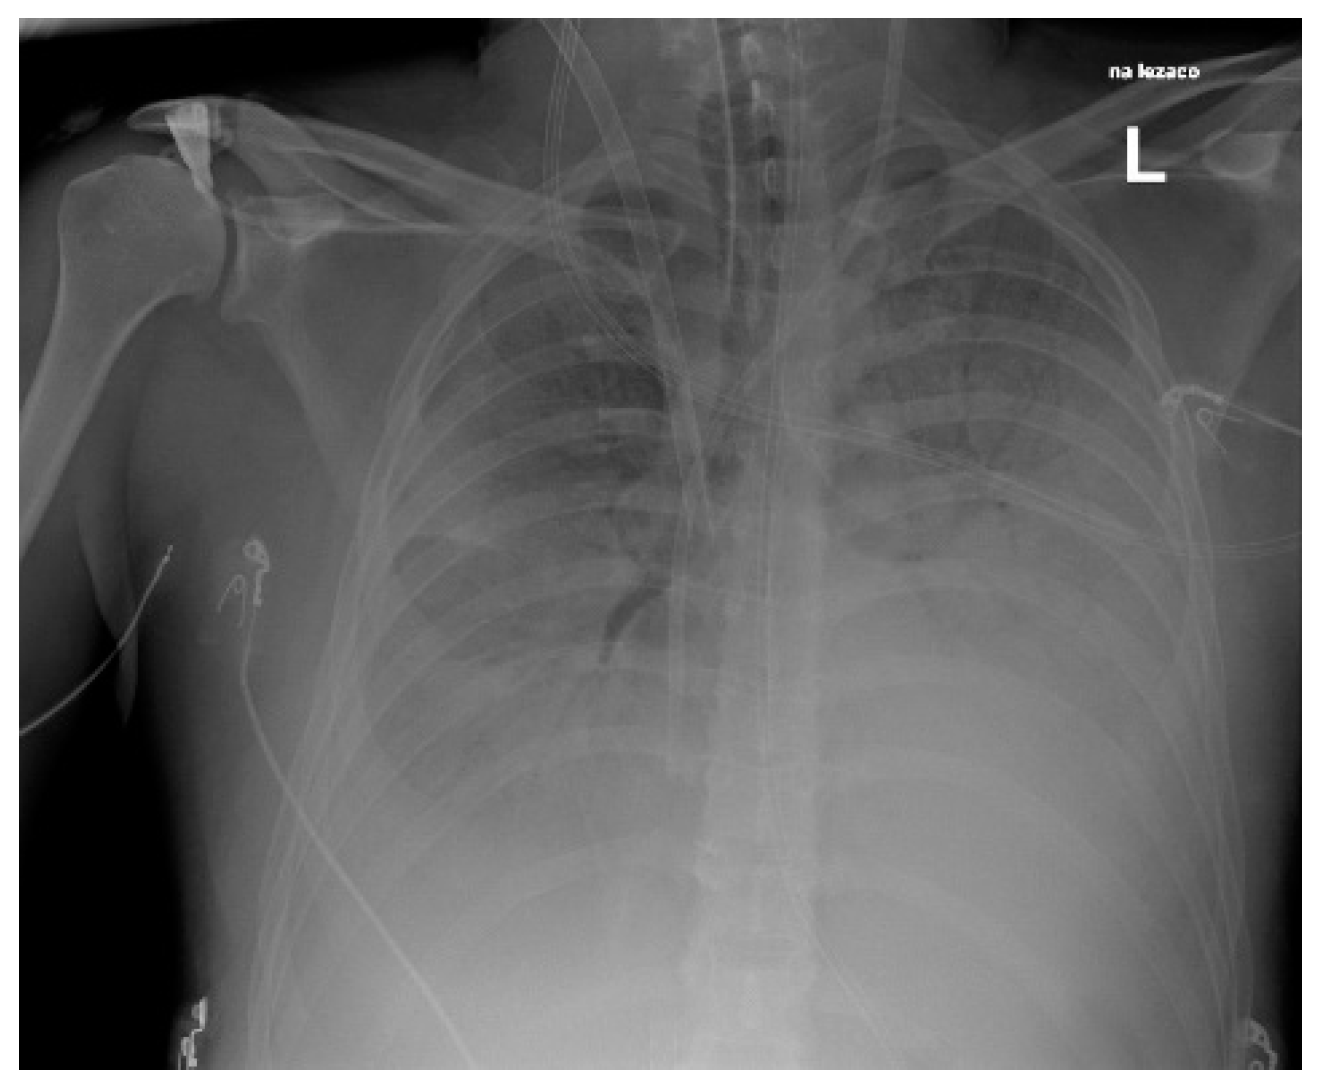

| 3 | 53/F | Cellulitis, mediastinitis | none | History of preceding infection | 17 | 7 | yes | 25 h | Died |

| 3 | Oxiris Cytosorb | no | blood culture + BCID2 b tissue biopsy | Linezolid Piperacilin/Tazobactam | Penicillin Clindamicin Linezolid |